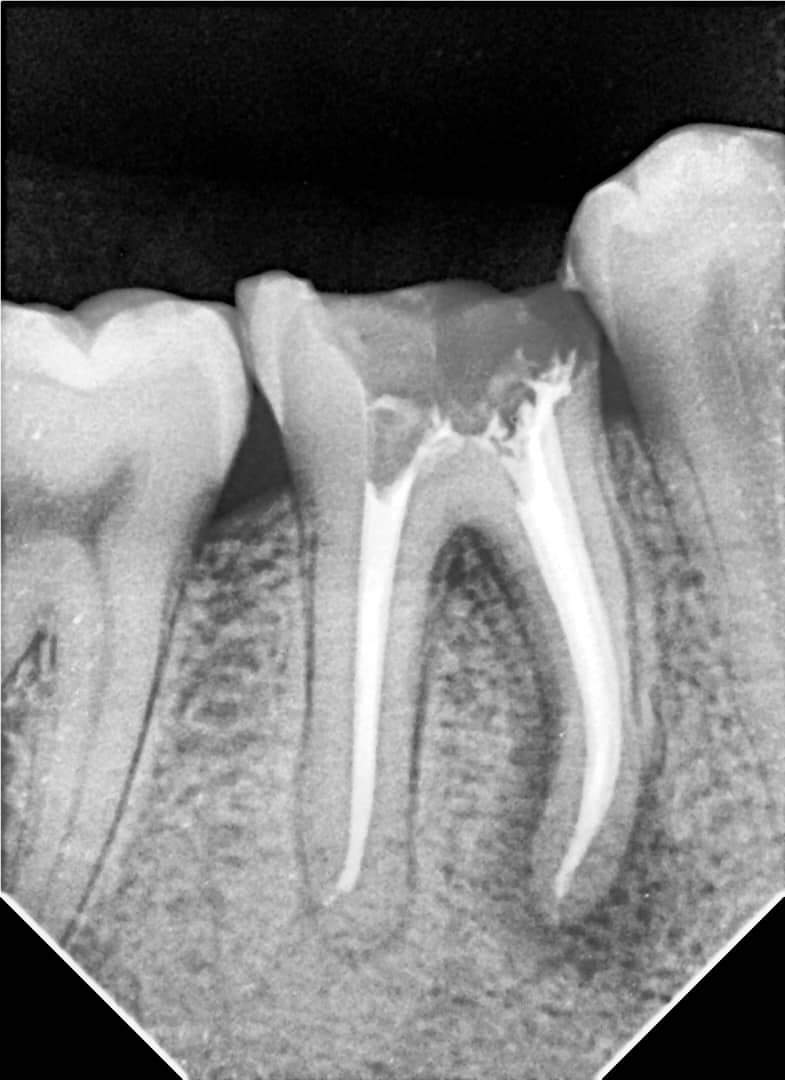

- Obturation with gutta-percha using the lateral condensation technique and AdSeal sealer

- Tooth restored with a zirconia crown

6-month follow-up:

Clinical and radiographic signs indicate successful healing of the periapical tissues.